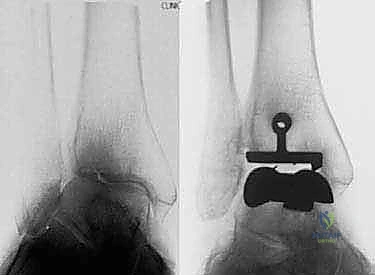

1. نظام سالتو لمفصل الكاحل الكلي (Salto Total Ankle Prosthesis - Mobile Bearing)

مفصل سالتو الأصلي هو ثمرة أبحاث أوروبية مكثفة. تم تطويره بين عامي 1994 و 1996، وبدأ استخدامه السريري بنجاح باهر في يناير 1997.

* التصميم الميكانيكي: يُعرف بأنه نظام ذو "مكون متحرك" (Mobile-bearing). يتكون من ثلاثة أجزاء رئيسية:

1. مكون معدني يثبت في أسفل عظمة الساق (Tibia).

2. مكون معدني يثبت في أعلى عظمة الكاحل (Talus).

3. قطعة بلاستيكية من البولي إيثيلين عالي الكثافة (Polyethylene insert): هذه القطعة ليست ثابتة، بل تنزلق بحرية بين المكونين المعدنيين.

* الميزة الكبرى: هذا التصميم يسمح بـ "التموضع الذاتي" (Self-alignment). أثناء الحركة، تتحرك القطعة البلاستيكية لتتكيف مع القوى الميكانيكية، مما يقلل من الضغط الواقع على واجهة التثبيت بين المعدن والعظم، ويحاكي حركة الكاحل المعقدة بشكل رائع.

* التثبيت: هو مفصل "غير إسمنتي". يتم تغطية الأسطح المعدنية الملامسة للعظم بطبقة مسامية من التيتانيوم وهيدروكسي أباتيت (Hydroxyapatite). هذه الطبقة تشجع العظم الطبيعي للمريض على النمو داخل مسام المفصل (Bone Ingrowth)، مما يوفر تثبيتاً بيولوجياً صلباً يدوم لسنوات طويلة.

2. نظام سالتو تالاريس (Salto-Talaris Prosthesis - Fixed Bearing)

بناءً على النجاح الهائل لنظام سالتو، تم تطوير نظام سالتو تالاريس لتلبية متطلبات مدارس جراحية مختلفة (خاصة في الولايات المتحدة).

* التصميم الميكانيكي: يشارك هذا النظام نفس الهندسة التشريحية الممتازة للمكونات المعدنية لنظام سالتو، ولكن مع اختلاف جوهري واحد: المكون البلاستيكي (البولي إيثيلين) هنا ثابت (Fixed-bearing) ويتم قفله بإحكام داخل المكون المعدني العلوي (الظنبوبي).

* الفلسفة وراء التصميم: أثبتت الأبحاث وخبرة الجراحين، بما في ذلك الأستاذ الدكتور محمد هطيف، أنه إذا تم إجراء القصات العظمية أثناء الجراحة بدقة متناهية تتوافق مع التشريح الطبيعي، فإن الحاجة إلى حركة واسعة للمكون البلاستيكي تقل بشكل كبير.

* الميزة الكبرى: نظام سالتو تالاريس يوفر استقراراً